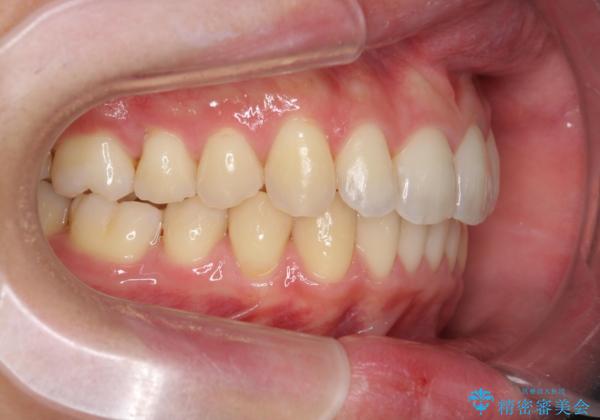

過蓋咬合・上顎前突・叢生を改善するマウスピース矯正

・前歯の深い噛み合わせ (過蓋咬合)

・上顎前突(Angle Class2)

・叢生(がたつき)

以上のような問題点をマウスピース矯正インビザラインとマイクロインプラントを用いて矯正治療を行い改善して行きます。

20時間以上のマウスピース装着、ゴムかけを遵守していただいたおかげでしっかりと噛み合わせ、がたつきの改善を行うことができました。